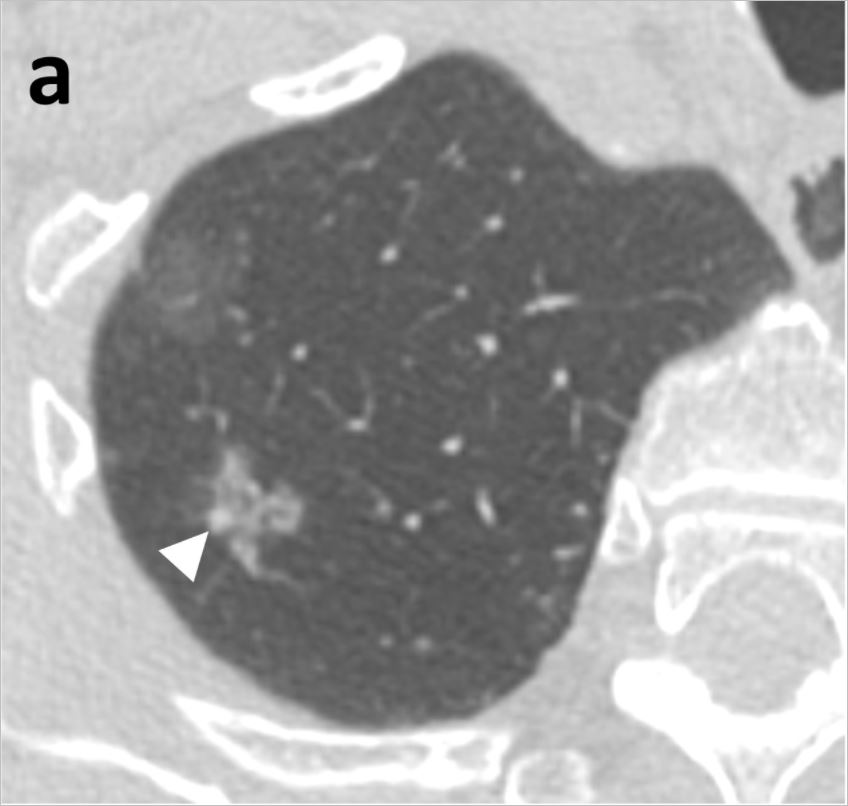

간유리 음영이란 CT로 폐를 촬영할 경우 영상에 뿌옇게 유리를 갈아 뿌려 놓은 것 같은 모양을 하고 있다면 붙여진 이름입니다. 아직까지 어떻게 치료해야 할지에 대해 명확한 기준이 나와 있지 않습니다. 최근 연구 결과에 의하면 간유리 음영의 대부분이 조직검사 결과 암이었다고 합니다.

연세대 강남세브란스병원 흉부외과 이성수, 문덕환 교수 연구팀은 2012년 5월부터 2016년 12월까지 강남세브란스병원에서 폐암이 의심돼 수술받은 환자 중 순수 간유리 음영으로 진단된 36명, 44례를 분석한 결과, 침윤성 선암이 10례(22.7%), 최소침윤성 선암이 15례(34.1%), 제자리암종 18례(40.9%), 비정형샘종증식이 1례(2.3%)로 나타났다고 24일 밝혔다. 제자리암종은 암세포가 기저막을 침윤하지 않고 상피층 내에만 있어 0기암이라고도 불리는데, 제자리암종까지 포함할 경우 간유리 음영 결절의 97% 이상이 암이었다는 뜻이다. 비정형샘종증식도 폐암이 되기 직전의 병변이기 때문에 사실상 분석한 간유리음영 모두 암으로 볼 수 있다고 연구팀은 설명했다.